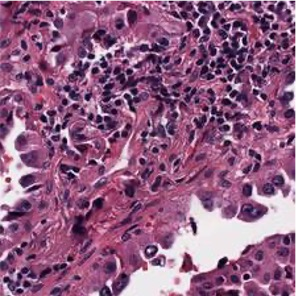

Multiple instance learning (MIL) is a powerful approach to classify whole slide images (WSIs) for diagnostic pathology. A fundamental challenge of MIL on WSI classification is to discover the \textit{critical instances} that trigger the bag label. However, previous methods are primarily designed under the independent and identical distribution hypothesis (\textit{i.i.d}), ignoring either the correlations between instances or heterogeneity of tumours. In this paper, we propose a novel multiplex-detection-based multiple instance learning (MDMIL) to tackle the issues above. Specifically, MDMIL is constructed by the internal query generation module (IQGM) and the multiplex detection module (MDM) and assisted by the memory-based contrastive loss during training. Firstly, IQGM gives the probability of instances and generates the internal query (IQ) for the subsequent MDM by aggregating highly reliable features after the distribution analysis. Secondly, the multiplex-detection cross-attention (MDCA) and multi-head self-attention (MHSA) in MDM cooperate to generate the final representations for the WSI. In this process, the IQ and trainable variational query (VQ) successfully build up the connections between instances and significantly improve the model's robustness toward heterogeneous tumours. At last, to further enforce constraints in the feature space and stabilize the training process, we adopt a memory-based contrastive loss, which is practicable for WSI classification even with a single sample as input in each iteration. We conduct experiments on three computational pathology datasets, e.g., CAMELYON16, TCGA-NSCLC, and TCGA-RCC datasets. The superior accuracy and AUC demonstrate the superiority of our proposed MDMIL over other state-of-the-art methods.